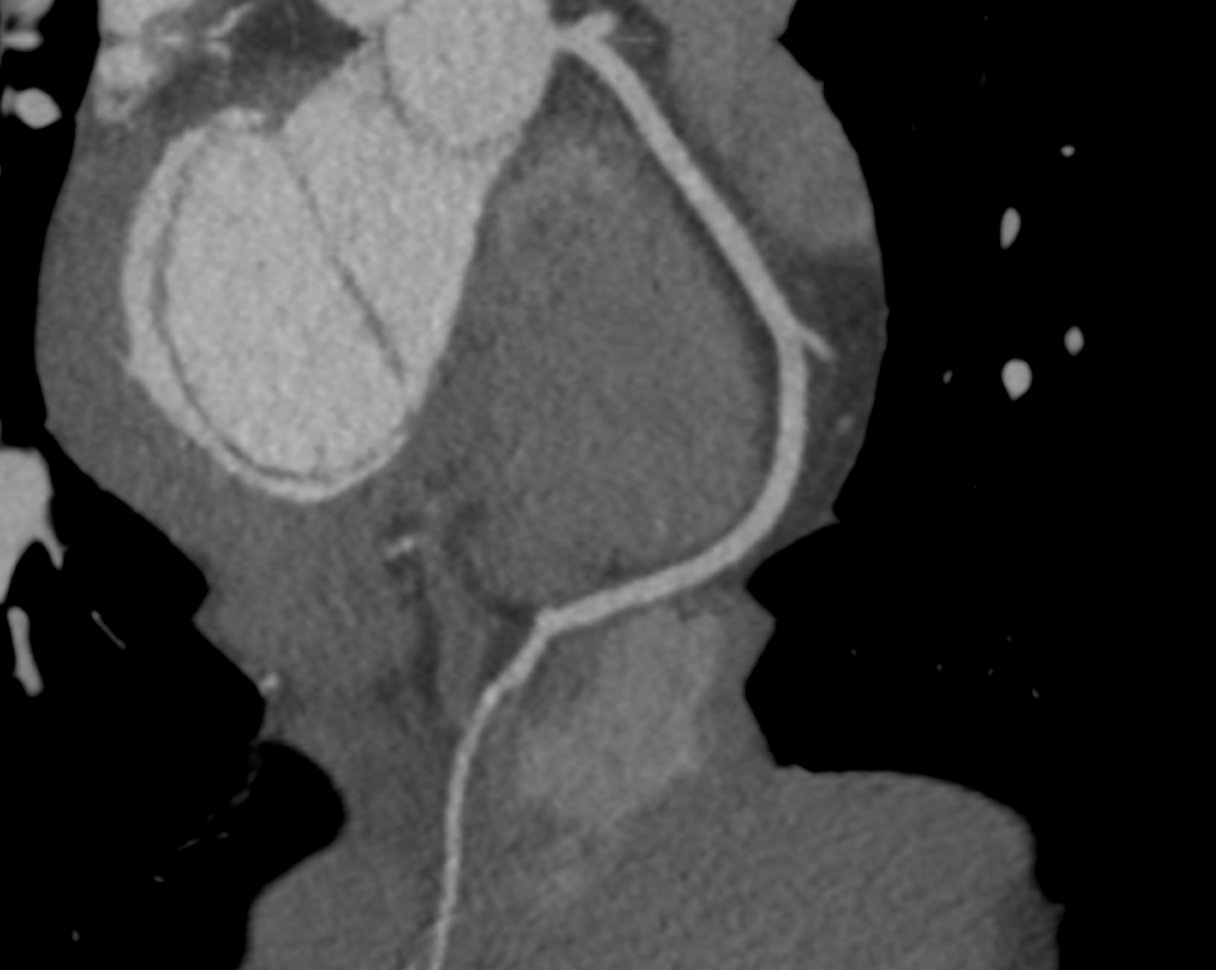

There is a world outside the stent mesh

Caso condiviso da Saima Mushtaq

Paziente con anamnesi di malattia coronarica e pregresso impianto di stent sulla discendente anteriore sinistra.

Per prima cosa, esamina l'intera scansione. Concentrati sul tronco comune e sulla porzione prossimale della discendente anteriore sinistra.